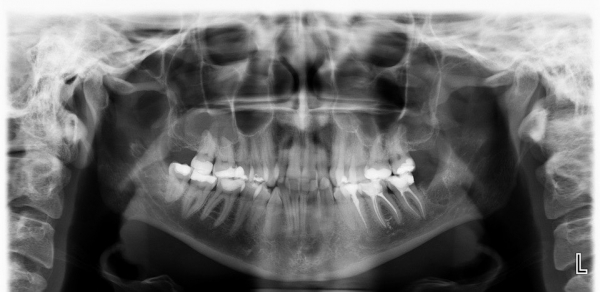

14 марта я удалила нижнюю восьмерку. Удалила, так как она росла криво, в щеку. Потом по стечению обстоятельств появился пульпит, рядом на семерке, вылечила. Потом заболела гриппом, ослабление иммунитета. Воспалились десны. Пропила курс витаминов, мазала десну. Потом заметила, что появились неприятные ощущения на противоположной стороне челюсти. Там где еще есть восьмерка. Ближе к десневой боли. Чувствуется когда прожевываешь твердую пищу, жуешь жвачку. Как будто что-то болит, но не сильно. Не острая боль. Не жуешь - не болит. Сделала снимок челюсти.

По снимкам никаких патологических изменений в области восьмерки нет. На ней установлена пломба либо керамическая вкладка, и конструкция вполне отвечает нормам.